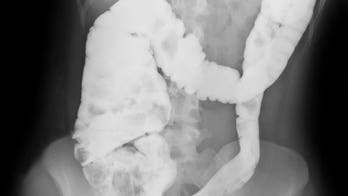

Digestive Health - Page 28